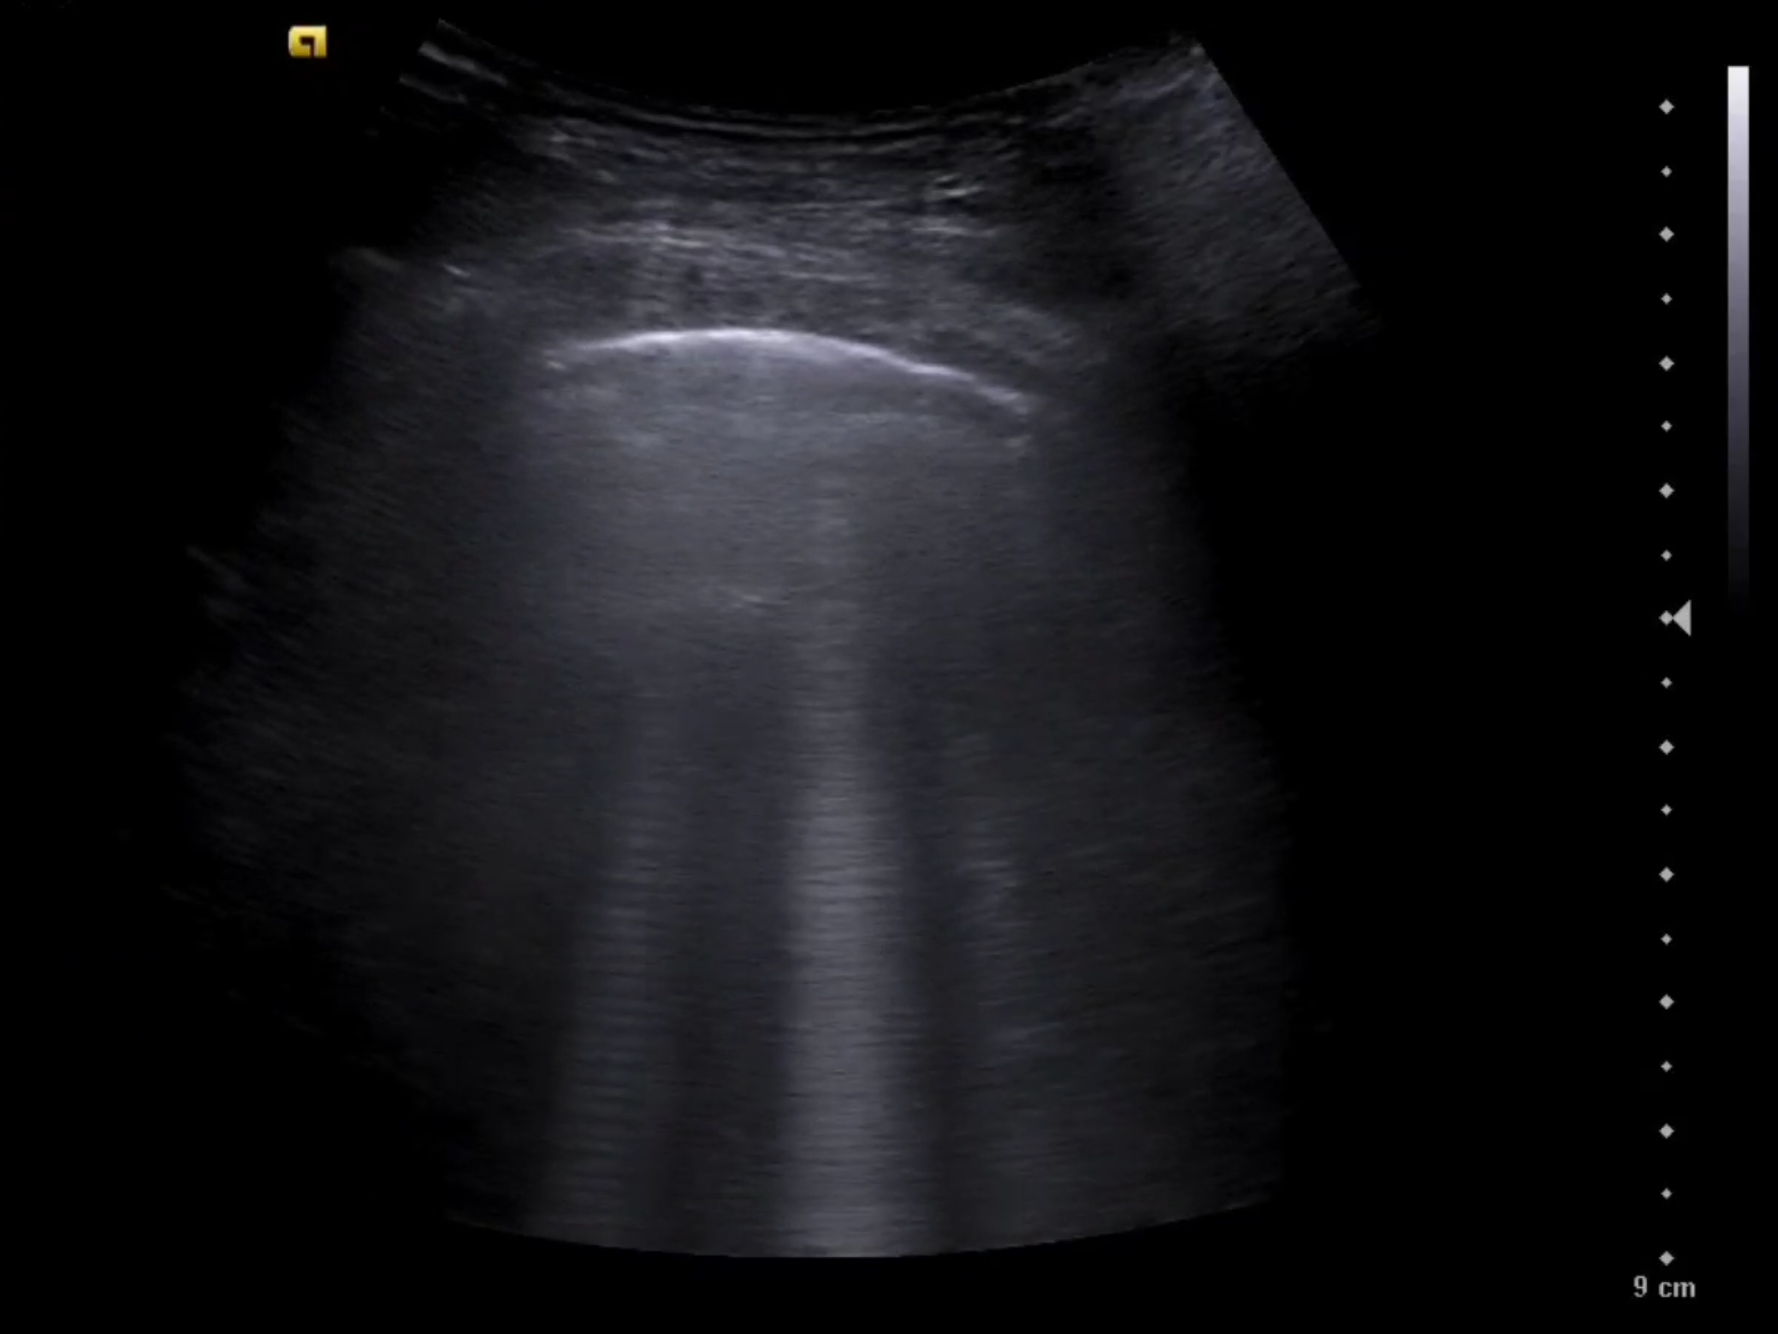

A las técnicas ya presentes en consulta como la ecografía abdominal a nivel de vena cava inferior (VCI) y ecografía pulmonar, se incorpora la ecocardioscopia y el protocolo VEXUS.

La sobrecarga de presión o volumen en un paciente provoca congestión intersticial, Nefrología aplica el protocolo VEXUS «Venous EXcess UltraSounds» tanto en el diagnóstico como en el seguimiento de múltiples patologías. Se han descrito 4 perfiles de congestión.

La ecografía complementa otras pruebas complementarias clásicas como: ECG, Rx Tórax y analítica (hierro, TSH, ProBNP y CEA125). Ya incorporadas, la ecografía abdominal para la VCI, la ecografía pulmonar y la ecocardioscopia, es el momento del protocolo VEXUS en el diagnóstico y seguimiemto de patologías como: Insuficiencia Cardíaca, s. CardioRenal o s. Nefrótico.